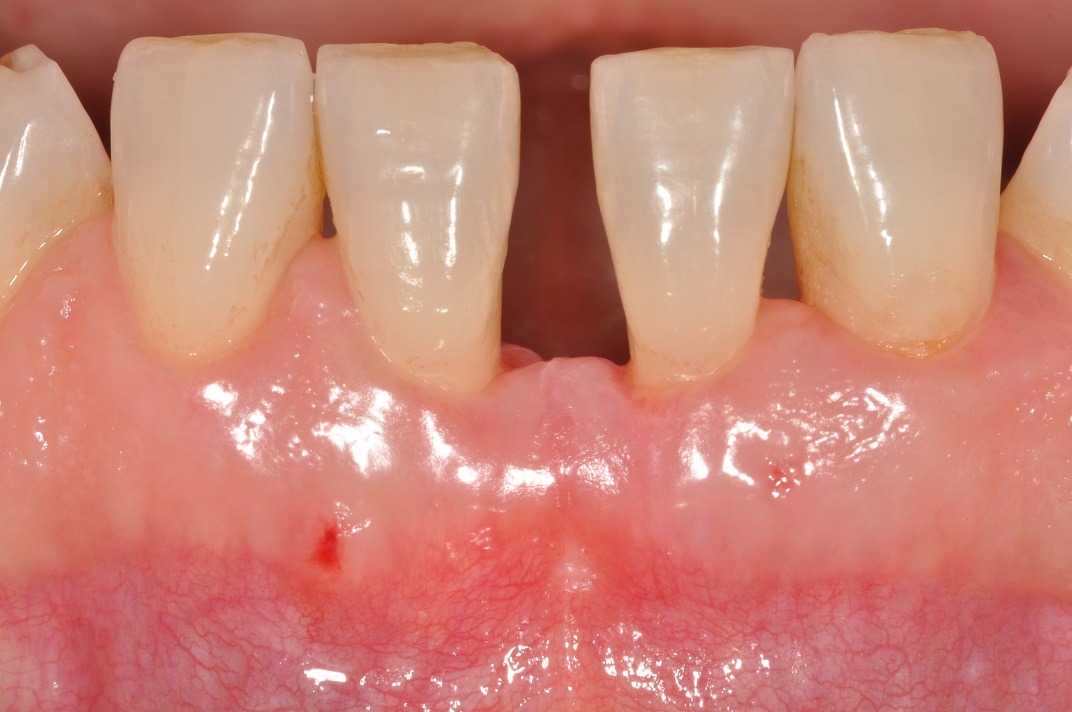

01/13 - Baseline clincial situation and pre-surgical probing.

Wide intrabony defect treated with the modified papilla preservation flap in conjunction with Straumann® Emdogain® and autogenous bone - Dr. B. Molnar